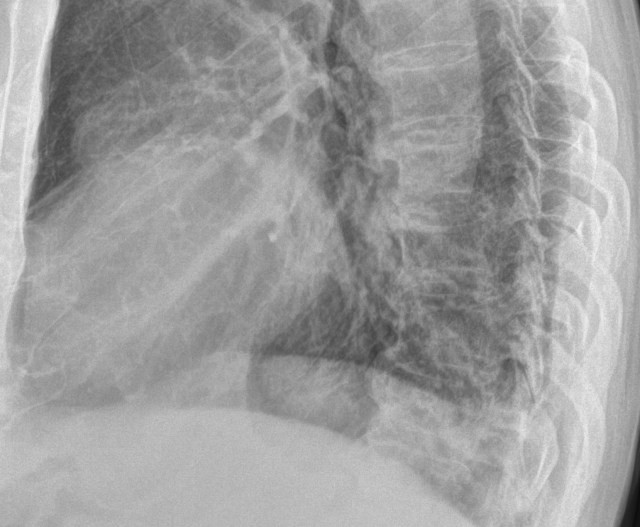

별다른 임상정보 없이 위와 같은 가슴사진이 판독할 리스트에 떳다고 해봅시다. 의학적인 지식이 전무한 일반인이라면, 당연히 이게 뭔지, 뭘 봐야 하는지조차 아무런 감이 없으실 겁니다. 바로 이런 단계를 투자영역에서는 “호구”라고 부를 수 있을겁니다.

사실 이 환자는 동네 의원에서 폐렴이 의심된다고 해서 내과로 입원한 분입니다. 당연히 폐렴의 가능성을 제일 먼저 확인해야 겠지요. 위 영상에서 뭔가 이상소견이 보이시는지요? 의대생이 졸업을 하기 전에 가슴사진에 대해 공부를 할 때 제일 중요하게 강조되는 개념이 “실루엣 징후”입니다. 사실, 의대생이라도 이 실루엣징후라는 것을 “제대로” 공부했다면 이 사진에서 무엇이 문제라는 걸 금방 알 수 있습니다. 어찌 되었든 간에 이게 흉부단순촬영 영상이라는 것, 그리고 환자의 임상증상을 볼 때 왜 이 사진을 촬영한 것인지 전후사정을 이해할 수 있다면 적어도 “뭔가를 좀 아는” 상태라고 할 수 있습니다. 투자영역으로 따지면 호구까지는 아니고 이제 첫걸음을 떼고 앞으로 나아갈 준비가 되있는 “초보”단계로 볼 수 있습니다.

하지만, 제가 지금까지 봐왔던 교과서, 원서들에서는 실루엣 징후라는 걸 상투적으로만 소개하고 있는게 현실입니다. 단순촬영 영상에서 어떤 병변이 주변 정상구조물의 윤곽을 가리고 있다면, 해당 병변의 위치가 그 구조물과 비슷한 위치라는걸 의미한다는 것. 그러므로 횡격막 윤곽이 가려지면 폐하엽, 우측 심장윤곽을 가리고 있다면 우중엽, 좌측 심장윤곽을 가리고 있다면 병변이 좌상엽의 설상엽에 위치한다는 정도를 언급하고 있을 뿐입니다.

좀 더 심도있게 다루는 경우라면 폐 바깥쪽이나 척추 근처에 위치한 병변에서 나오는 실루엣징후를 언급하기도 하지만, 더 나아가 폐혈관이 가지를 치면서 뻗어가는 모양에 변화가 있는지를 확인하라는 충고를 하는 교과서는 없습니다. 때문에, 이 환자가 폐렴이 의심되는 임상증상으로 내원했다는 정보를 가지고 있는 주치의나 내과의사라 하더라도, 위의 영상에서 어디가 문제가 있다는 걸 짐작하는건 쉽지 않습니다. 다만, 증상이 분명히 있는데 영상에서 뭔가가 나오지 않을 때, “그 다음에는 무엇을 해야 하는지”에 대해서 생각하고 실행에 옮길 줄 안다면, 그것은 최소한 돌팔이는 아니라고 할 수 있을겁니다. 환자분의 증상이 호전되지 않는다면 옆에서 촬영해본다던지, CT를 찍어볼 수 있습니다.